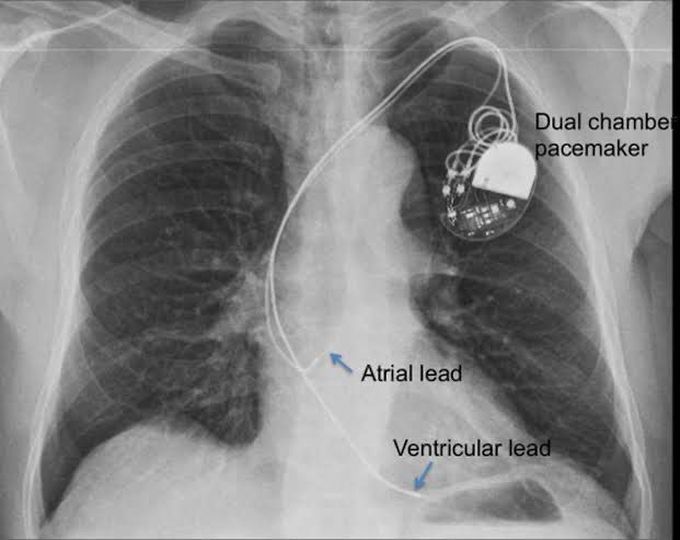

Pacemaker is a small electrical device placed under the skin to help the heart beating. It is used in people suffering from heart abnormalities like conduction defects, heart blocks, AV or SA Node dysfunction, After Acute Phase of Myocardial Infarction, Post-cardiac transplantation, etc. The Chest X-ray shows the pacemaker with its two leads i.e. atrial and ventricular leads. Picture credit: https://johnsonfrancis.org/professional/dual-chamber-pacemaker-chest-x-ray/amp/